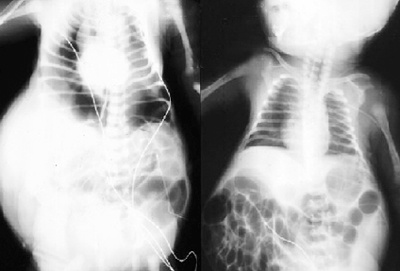

![]() |

| Hình ảnh tổn thương mất cơ bụng trên phim Xquang. |

Nếu siêu âm trong thời kỳ thai nghén có thể thấy sự phát triển bất thường của bàng quang và đường tiết niệu của thai nhi. Trong khi thai nhi phát triển, dịch tiết ra trong bụng ngày càng lan rộng nhiều hơn. Nhưng chất lỏng được tái hấp thu trước khi sinh, cho nên khi sinh ra, bụng của đứa trẻ bị võng hoặc da nhăn nheo. Sau khi sinh, siêu âm và chụp Xquang có thể xác định được các tổn thương bất thường về đường tiết niệu.

Dấu hiệu dễ nhận thấy nhất của bệnh là bụng trẻ sơ sinh to bất thường, da vùng bụng nhăn nheo. Trẻ sơ sinh thường xuyên bị viêm đường tiết niệu. Xét nghiệm máu, nước tiểu kiểm tra chức năng thận thấy các triệu chứng viêm nhiễm và suy thận.Bất thường về cơ xương khớp bao gồm: vẹo cột sống, trật khớp bẩm sinh, có thể bị trật cả khớp hông. Vì vậy, chẩn đoán hội chứng mất cơ bụng đòi hỏi đánh giá chỉnh hình kỹ lưỡng vì tỷ lệ cao bất thường của cơ xương liên quan.